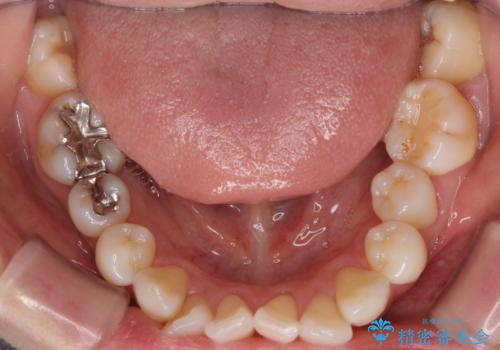

- リンガル

上下裏側矯正であったため、舌に傷や口内炎ができるなどつらい経験もされましたが、目立たずに治療できたことに喜んでいただけました。